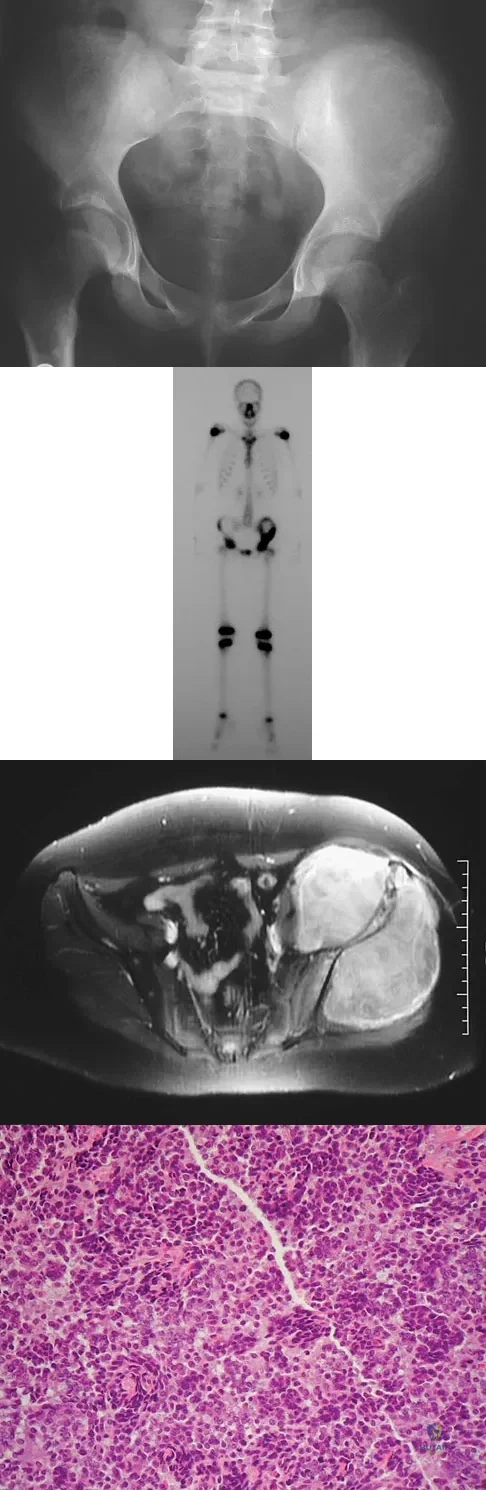

A 13-year-old girl has had increasing left hip pain for the past 4 months. A radiograph, bone scan, MRI scan, and photomicrograph are shown in Figures 1a through 1d. Which of the following immunohistochemistry results would confirm the most likely diagnosis?

Explanation